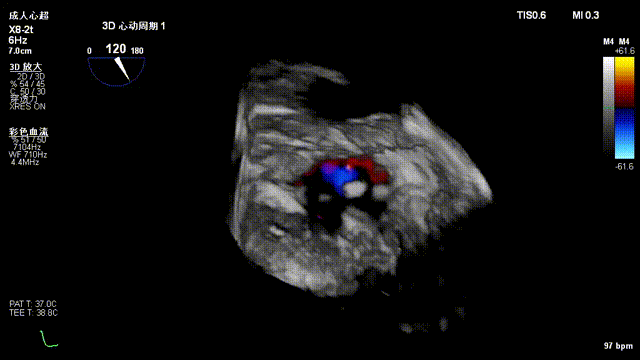

手术采用左侧第六肋间微创切口心尖入路,在超声Mutlivue引导下清晰识别MitraFix®输送系统准确跨瓣,并将人工瓣膜准确释放于二尖瓣瓣环,瓣膜释放后支架贴合牢固,术后无瓣内反流及瓣周漏,二尖瓣前向血流通畅、跨瓣压差2mmHg,左心室流出道通畅,流出道血流速度0.8m/s,后顺利撤出输送系统,关闭心尖切口,手术顺利结束。

术后无反流